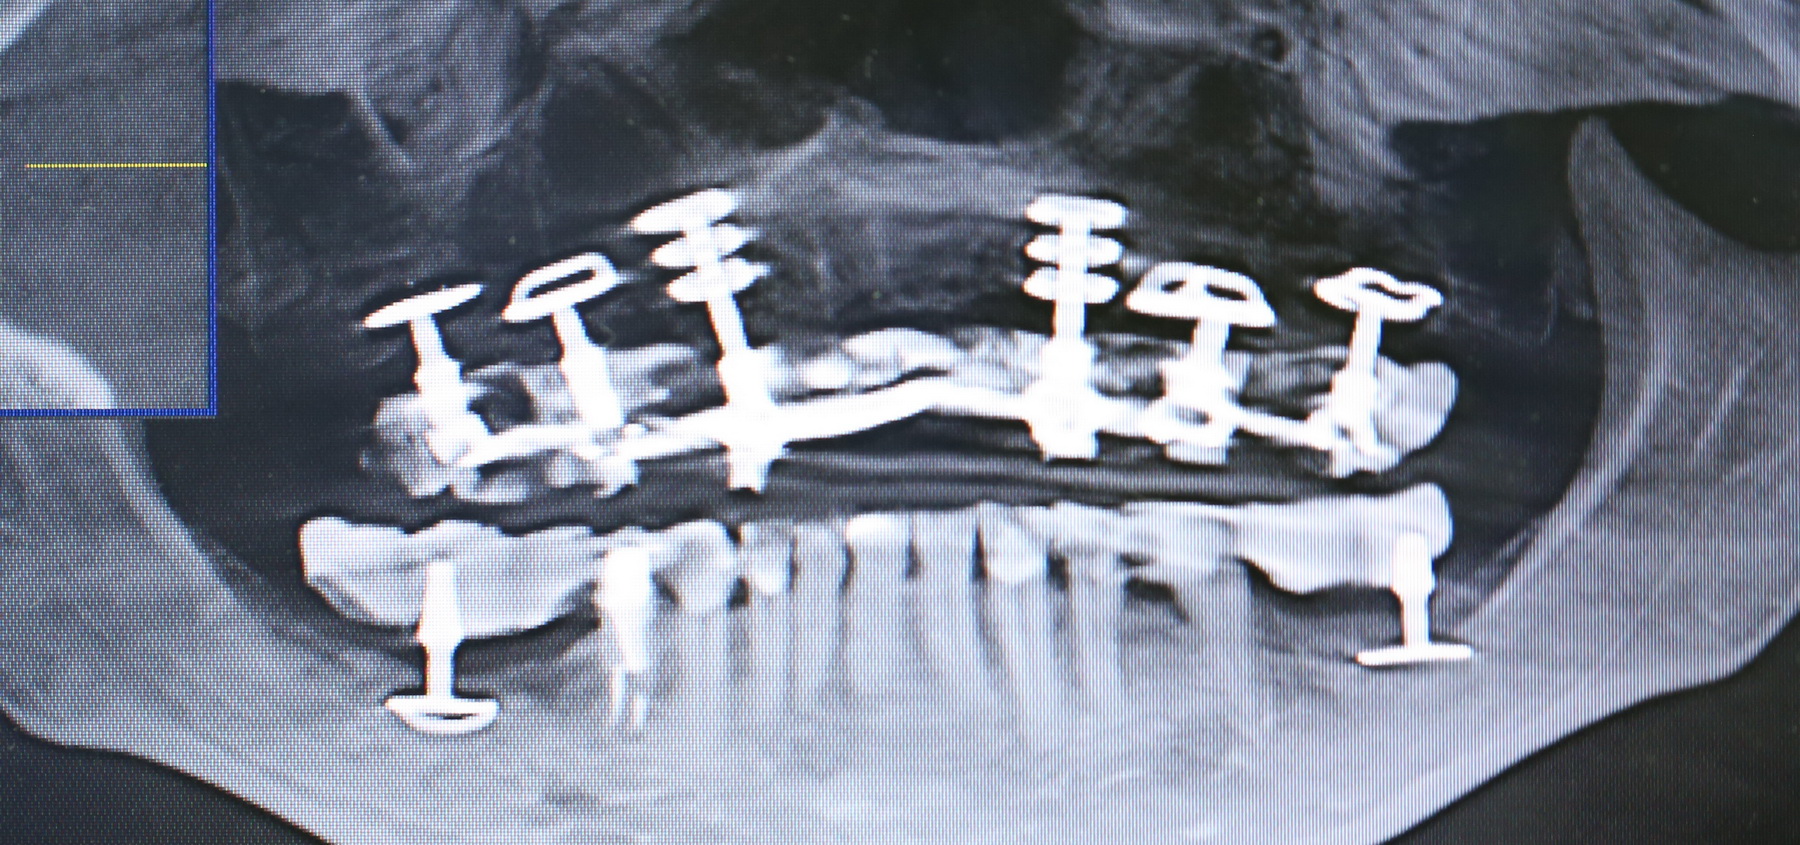

Прикольно) Прокомментирую картинкой под названием «Удаление зуба мудрости: Дашков versus какой-то доктор из Челябинска». С учетом того, что у Пашкульского финансовый план составляет куратор лечения (так он написал в нашем ТГ-канале), он же готовит пациента к операции, дает список анализов и т. д.: